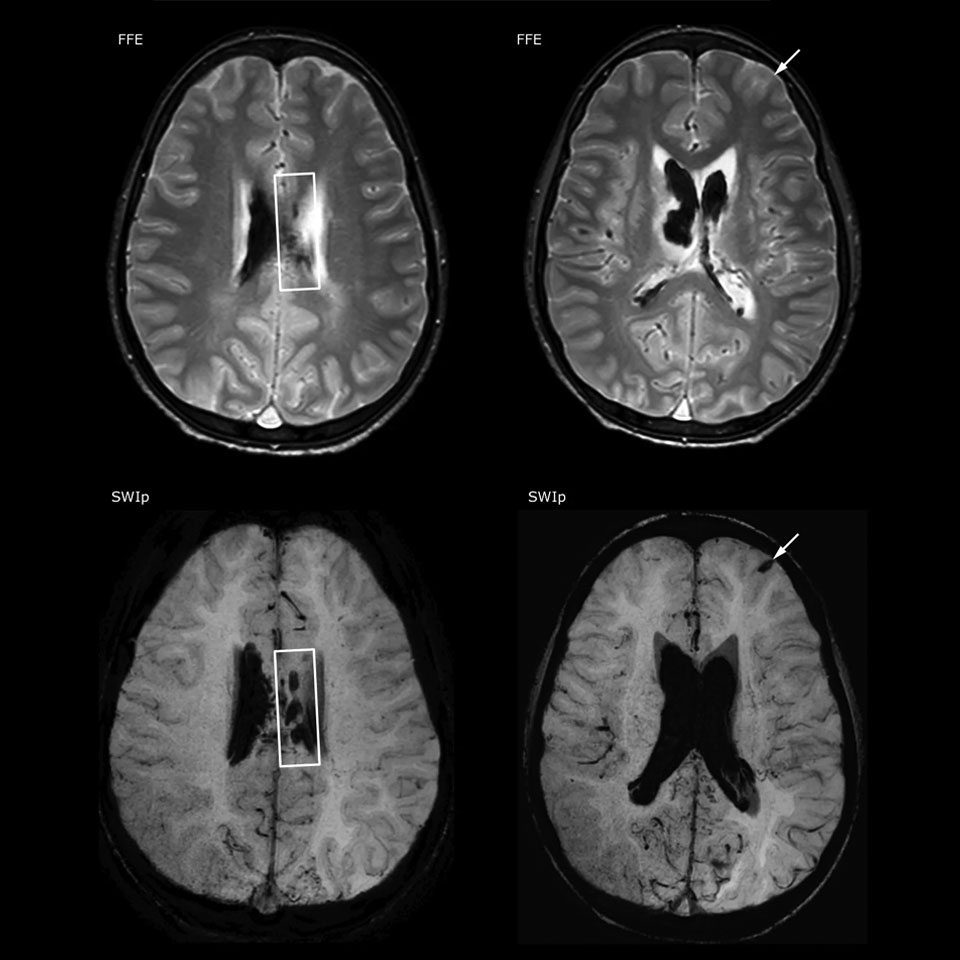

The value of susceptibility weighted imaging in visualizing brain injury is well documented. The Philips multi-echo SWIp technique provides fast susceptibility weighted imaging with enhanced susceptibility contrast and high resolution.

“SWIp helps us identify blood or blood products, calcification, and diseases that affect the vascular system,” says Dr. Miller. “In children with traumatic brain injuries, it highlights areas that are injured, better than some of the previous techniques that we were using. These children often have micro-injuries that cause small amounts of blood or tissue damage. Adding SWIp helps us to better characterize the extent and nature of the injury. Having characterized an injury to the extent of what’s possible supports our diagnostic confidence.”

“I would definitely recommend other users to implement SWIp. We initially added the SWIp sequence following a lot of support for its utility in the literature. Then we directly compared SWIp to the 2D gradient echo sequences that we were using. After a good amount of clinical experience in seeing its benefits, we were confident to replace the old sequences with SWIp. It gives us a better assessment of the physiological processes of the brain that were less apparent on our previous imaging sequences,” says Dr. Miller. “SWIp is now a routine sequence for imaging traumatic brain injury patients at PCH, and it’s episodically added for patients who have intracranial vascular abnormalities.”

“I believe SWIp is rapidly becoming the standard in imaging traumatic brain injury, because of its high sensitivity to venous blood products. SWIp may even help attract patients; our neurosurgeons often ask to have the patients imaged on our scanners with highly sensitive techniques like SWIp. There’s also a growing application of SWI sequences in other vascular abnormalities because of the possibilities around physiological assessment of the brain than just a standard structural imaging.”